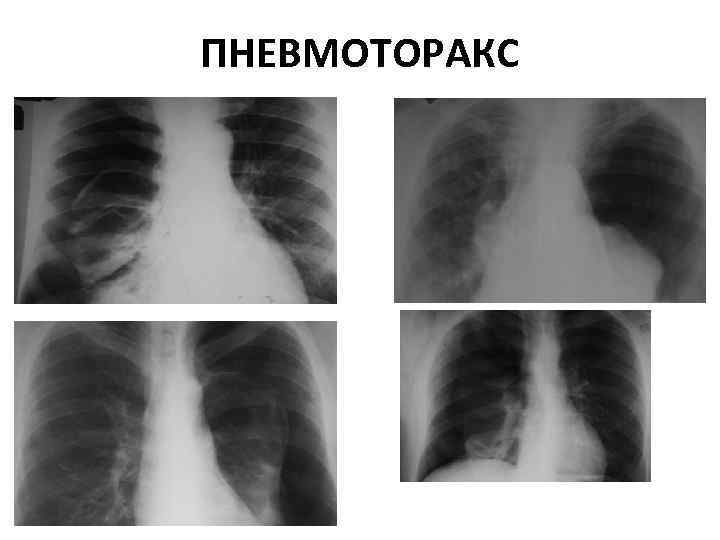

ПНЕВМОТОРАКС